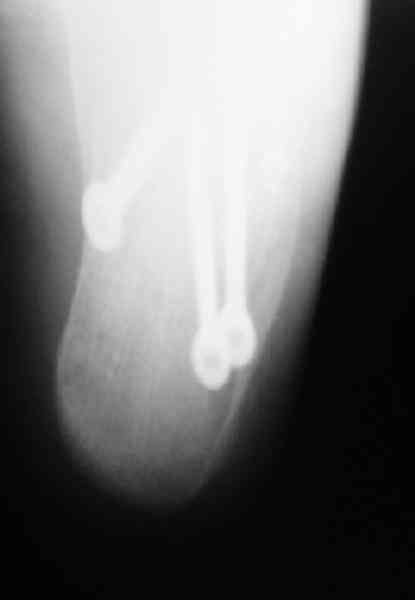

Re: Перелом пяточной кости

Пяточной пластиной

Открытый и закрытый способы лечения.